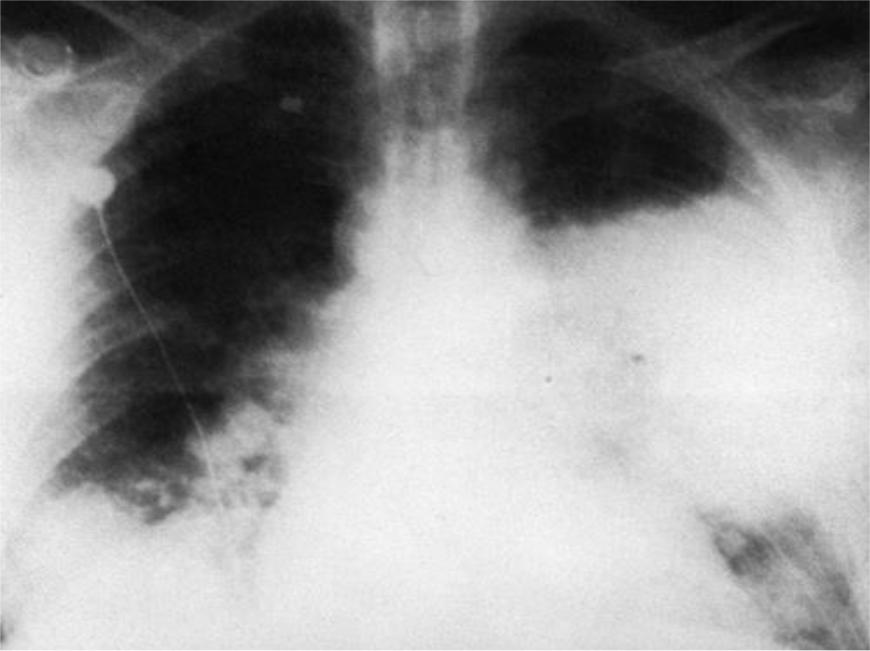

Острая внебольничная пневмония по МКБ-10: признаки и примеры